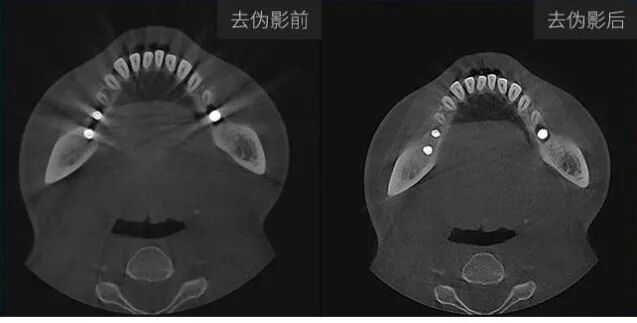

去除金属伪影,使图像更加清晰流畅,易于诊断